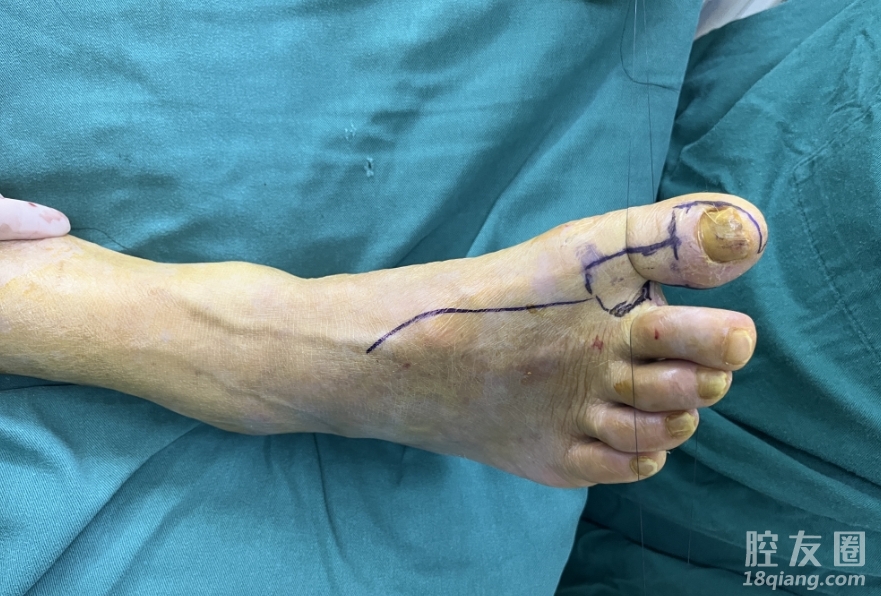

杨锦介绍,根据老江的情况,团队为其量身定制了分期移植的手术方案,一期手术对右拇指残端进行了细致清创处理;二期手术最为关键,需要根据缺损大小在患者右足踇趾腓侧精准设计带趾骨踇甲瓣进行移植。

手术中,杨锦主任医师团队小心游离解剖右踇趾血管神经,游离髂骨组合移植,以最大限度保证再造大拇指的长度和功能,又能大大降低对右足踇趾供区的破坏。